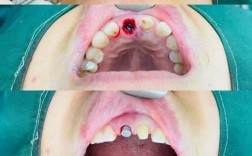

- 牙龈退缩: 牙龈边缘向根方退缩,暴露种植体颈部甚至部分种植体表面。

- 种植体松动: 这是最严重的信号之一。 轻度松动可能仅在咬硬物或特定方向时感觉到,重度松动则肉眼可见或用手晃动即可察觉。

- 种植体周围X线片显示骨吸收: 这是诊断和评估严重程度的关键,可以看到种植体周围牙槽骨高度降低,形成“骨陷窝”。